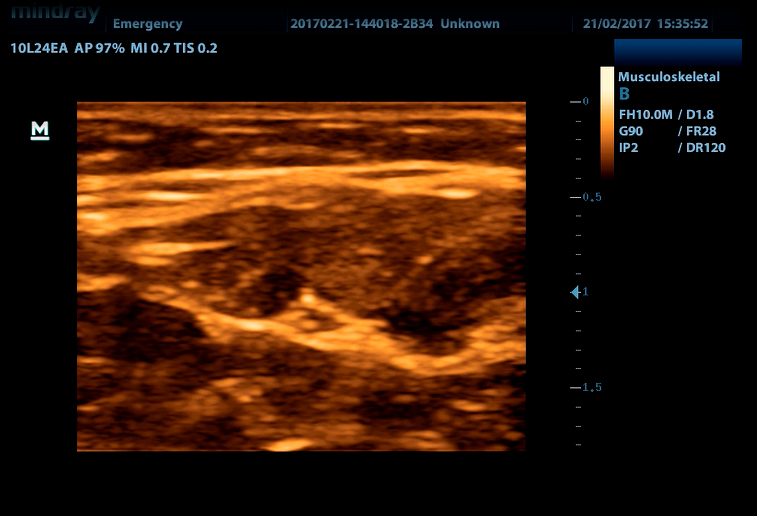

УЗ-сканер DP-50 Color представляет собой новое поколение ультразвуковых систем с цветных доплером компании Mindray. Он оснащен передовыми технологиями визуализации, обеспечивающими более глубокое проникновение и быстрое получение изображений при более высоком разрешении. УЗ-сканер DP-50 color отлично подходит для всех клинических ситуаций благодаря своей новой высокотехнологичной конструкции, повышенной мобильности и удобству эксплуатации.

- Широкий выбор мультичастотных датчиков от 2,0 до 14,0 МГц

iBeam Позволяет использовать несколько углов сканирования для формирования единого изображения, что приводит к увеличению контрастного разрешения и улучшению визуализации.

iClear Позволяет улучшить качество изображения, основываясь на автоматическом распознавании структур.

- Линейный датчик 75L38EA, 3.3 - 13.0 МГц, апертура 38 мм